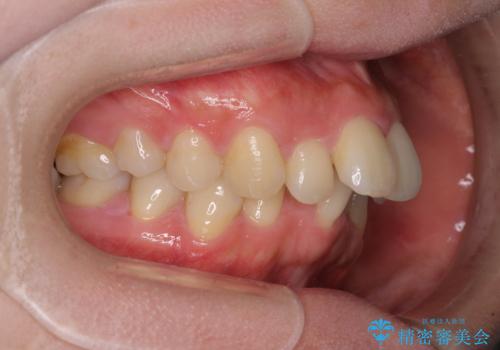

全顎的なデコボコと口元の突出感 ワイヤー装置での抜歯矯正で整った口元に

- 奥歯も含めて全体的なデコボコと前歯の突出感を気にして来院された患者様です。

上下左右第一小臼歯4本を抜歯し、ワイヤー装置にて矯正治療を行うこととしました。

想像以上に咬合力が強く、抜歯したスペースを閉じきるまでに長期間を要することとなりました。

前歯の突出感がなくなり、仕上がりには大変満足していただけました。